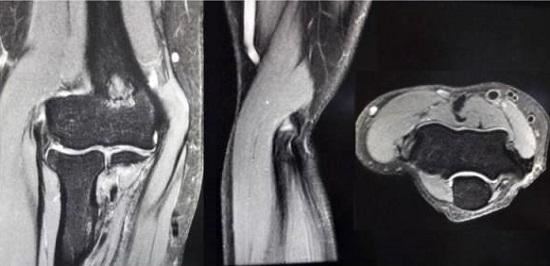

网球肘影像